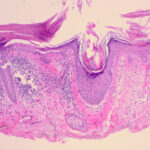

Histopathology

Actinic keratoses are keratinocytic dysplasias or squamous cell carcinomas in situ. This definition is preferable to their designation as precancerous because most of them never progress to cancers. Biologically, the lesions are still benign; invasion into the dermis, if present at all, is limited to the most superficial portion, the papillary dermis (see Differential Diagnosis) . |

This variety of keratosis, sometimes referred to as florid keratosis, may easily be overdiagnosed as invasive squamous cell carcinoma by the unwary. Mild or moderate papillomatosis may be present. The epidermis is thickened in most areas and shows irregular downward proliferation that is limited to the uppermost dermis and does not represent frank invasion .A varying proportion of the keratinocytes in the stratum malpighii show a loss of polarity and thus a disorderly arrangement. Some of these cells show pleomorphism and atypicality (“anaplasia”) of their nuclei, which appear large, irregular, and hyperchromatic. Often the nuclei in the basal layer are closely crowded together. Some of the cells in the midportion of the epidermis show premature keratinization, resulting in dyskeratotic cells or apoptotic bodies characterized by homogeneous, eosinophilic cytoplasm with or without a nucleus. In contrast to the epidermal keratinocytes, the cells of the hair follicles and eccrine ducts that penetrate the epidermis within actinic keratoses retain their normal appearance and keratinize normally. Occasionally, cells of the normal adnexal epithelium extend over the atypical cells of the epidermis in an umbrella-like fashion. In some cases, abnormal keratinocytes extend downward on the outside of the follicular infundibulum to the level of the sebaceous duct and, less commonly, along the eccrine duct . |

In the atrophic type of actinic keratosis, hyperkeratosis usually is slight. The epidermis is thinned and devoid of rete ridges. Atypicality of the cells is found predominantly in the basal cell layer, which consists of cells with large hyperchromatic nuclei that lie close together. The atypical basal layer may proliferate into the dermis as buds and ductlike structures. It may also surround as cell mantles the upper portion of pilosebaceous follicles and sweat ducts, the epithelium of which otherwise appears normal . |